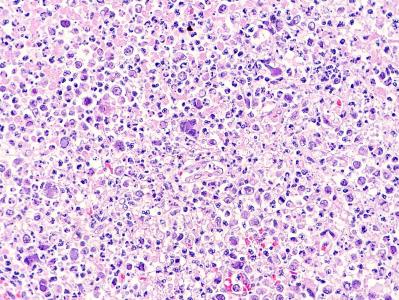

Este estudio, publicado en Transboundary and Emerging Diseases (2020; doi:10.1111/tbed.13713), ilustra el papel de la patología como herramienta de apoyo a los programas de conservación para especies en peligro de extinción. En este caso, la detección de dos herpesvirus presumiblemente nuevos en visones europeos se realizó a raíz del diagnóstico de un caso de linfoma principalmente neural/perineural con cuerpos de inclusión característicos de herpesvirus intralesionales en un visón europeo procedente del programa de cría en cautividad de esta especie amenazada. Estos virus podrían tener una influencia en el desarrollo de ésta y otras enfermedades que afectan a esta especie en cautividad y, por lo tanto, afectar a sus poblaciones.